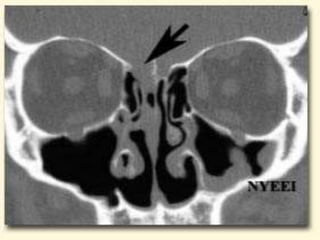

 Severe nasalcavity soft tissue thickening  Hypoattenuating mucosal thickening within lumen of paranasal sinus  Rapid aggressive bone destruction of sinus walls  Fungi can also spread along vessels with spread beyond the sinus with intact bony walls  Intracranial extension  cavernous sinus thrombosis  carotid artery invasion or occlusion

• 18.

 Unilateral ethmoidinvolvement with bone destruction, intraorbital spread and proptosis